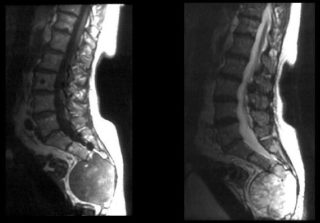

Остеохондроз

Остеохондроз — это патологический процесс, характеризующийся дегенеративно-дистрофическими изменениями в позвоночнике. В первую очередь страдают межпозвоночные диски: они истончаются, стираются и разрушаются. Это приводит к различным проблемам, включая ущемление нервов и сосудов, сильные боли, неврологические расстройства и образование грыж.

Появление шишек при остеохондрозе указывает на несколько неблагоприятных факторов:

- Разрастание остеофитов.

- Образование грыжи.

- Припухлость из-за воспалительного процесса и другие.

Эти образования различаются по структуре и размеру, но их объединяют общие черты. Во-первых, всегда присутствуют болезненные ощущения. Во-вторых, шишки возникают вблизи позвоночного столба или на нем, часто между позвонками.